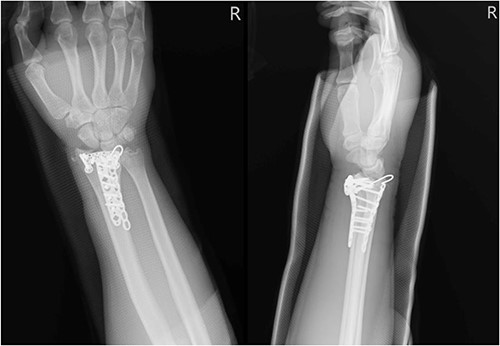

A 35-year-old male with no significant medical history fell from a third-floor balcony while working in February 2022, resulting in a right distal radius fracture that was treated with volar plate fixation. However, during an outpatient visit in November 2022, he reported a right thumb weakness that had been present for 3–4 months. Right wrist X-ray showed fracture at distal radius and carpal bones, s/p internal fixation (Fig. 5). A sonogram revealed a right thumb flexor tendon injury (Fig. 6), and he was admitted to our orthopedic ward for surgical repair of the FPL rupture on 12 November 2022. During the operation, plastic surgeon was consulted to repair the FPL rupture with a PL graft, repair the radial artery rupture and vessel with graft, repair the carpal ligament with left tensor fascia lata, release scar contracture of the volar and dorsal carpal region, and perform neurolysis of the median nerve due to adhesion to the FPL tendon.

Right wrist X-ray showing a fracture located at the distal radius and carpal bones, which was surgically treated with internal fixation.